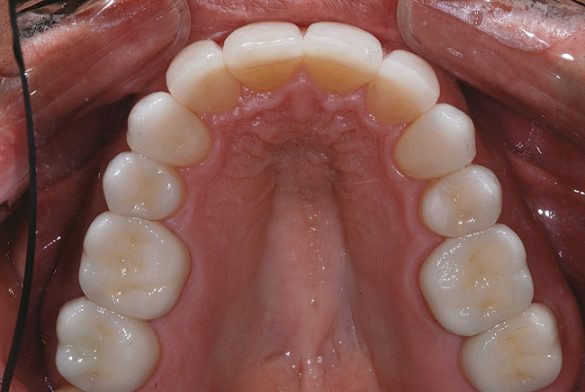

Spre deosebire de amprentele tradiţionale din polivinil-siloxan (PVS) în care toţi dinţii restauraţi trebuie retractaţi şi izolaţi în acelaşi timp, aparatul de scanare orală permite capturarea, la nevoie, a secţiunilor. După finalizarea amprentării digitale, în câteva zile modelele SLA răşinoase se recepţionează de laborator, se aplică pinuri, se secţionează şi sunt pregătite de montare şi fabricarea restaurărilor restante (fig. 7).

Molarii au fost prevăzuţi cu restaurări provizorii utilizând aceeaşi tehnică descrisă anterior. La returnare, coroanele finale au fost probate pentru verificarea contactelor proximale; adaptarea a fost minimă pentru că modelele răşinice SLA sunt extrem de exacte şi durabile.